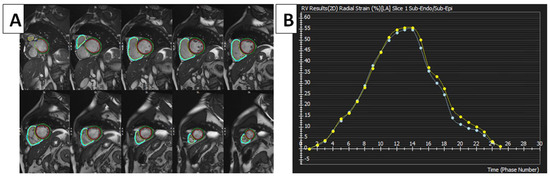

Figure 1.

FTI strain measurements of RV using cMRI tissue-tracking software (cvi42 version 5, Circle Cardiovascular Imaging Inc., Calgary, AB, Canada). (A) FTI with radial strain overlaid on short-axis cine SSFP image. Green circle: epicardium of LV; red circle: endocardium of LV; blue circle: epicardium of RV; yellow circle: endocardium of RV. (B) RV global radial strain. Radial strain values are usually positive. On the graph, the vertical axis shows the radial strain and the horizontal axis shows the time in milliseconds. FTI, feature tracking imaging; RV, right ventricle; LV, left ventricle; cMRI, cardiac magnetic resonance imaging; SSFP, steady-state free precession.